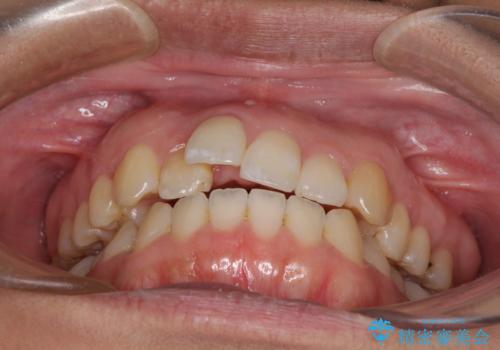

- 上下のデコボコを改善したいとのことで来院された患者様です。

近々妊娠する予定であり、極力短期間で治療したいとのことで、ワイヤー装置による非抜歯矯正治療を行うこととしました。